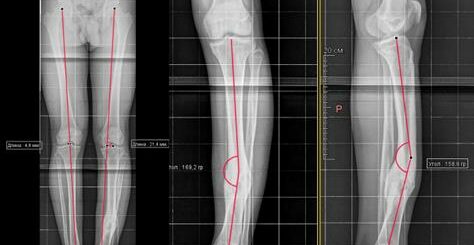

Diagnosis: Post-traumatic deformity of the first finger of the right hand, non-healing fracture of the proximal phalanx of the finger, osteosynthesis of the phalanx of the finger with a bone plate. Old injury to the tendon of the long extensor of the first finger of the hand. contracture of the interosseous joint of the first finger of the right hand.

Surgery: Revision, removal of foreign bodies of the first finger of the right hand. Autologous bone grafting of the defect of the MF of the first finger with bone from the crest of the right iliac bone. Osteosynthesis with the Ilizarov apparatus of the first ray of the right hand.

| Radiograph of the patient before treatment and after plate removal and osteosynthesis | |